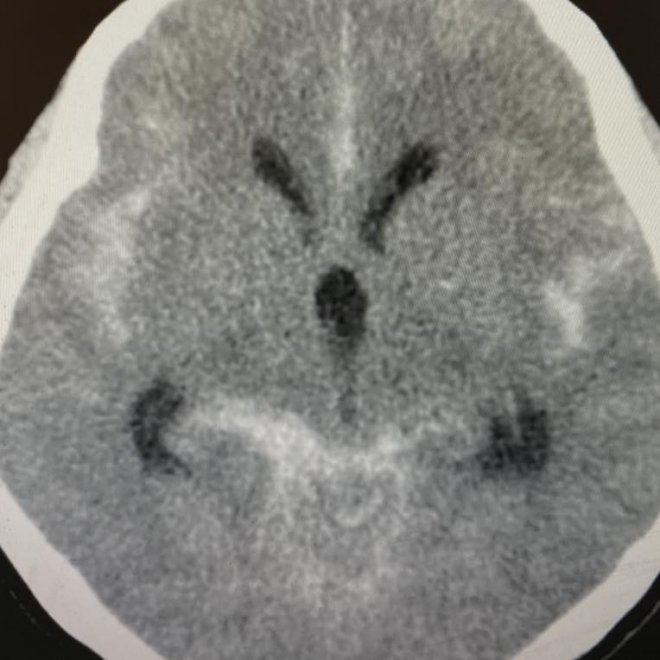

原來是有一次開票之夜,她曾遇到一位阿嬤支持者情緒太過激動,結果腦血管破裂,被送到醫院,送來時已經嘴角歪一邊、說話含糊不清,「只聽得懂『凍蒜』、『凍~~』」。當時阿嬤血壓飆到198mmHg,一照片子動脈瘤破裂。

緊急幫阿嬤做了腦部動脈瘤栓塞手術,但腦部出血造成腦水腫,後來必須開腦再放個引流管減輕腦部壓力,最終成功將阿嬤從鬼門關前救回一命。讓她直呼「但真的得不償失呀!」